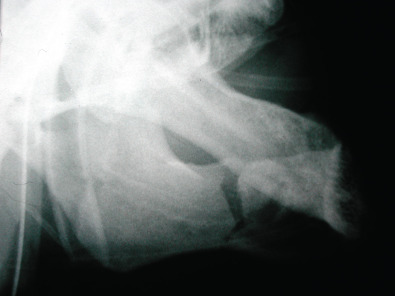

If maxillofacial trauma is suspected, radiographs will most likely be performed. Plain films of the maxillofacial region such as the mandible series, Waters view and submental vertex view are almost always now being replaced by the computed tomography (CT) scan. CT scans of the maxillofacial region give much better detail in a 3-dimensional aspect to assist the provider in diagnosing the injury and formulating a treatment plan. Occasionally, patients seen in the outpatient office will have an orthopantomogram (panorex) as a screening film for mandibular trauma. The orthopantomogram should have another radiograph in a second plane such as an AP film or CT scan to fully assess the injury. A CT scan is the optimal study to assess maxillary and upper face trauma. Additionally, the CT scan can be carried through the skull to assess bony and soft tissue injuries to the central nervous system and cervical spine ( Figs. 1.21.3–1.21.6 ).